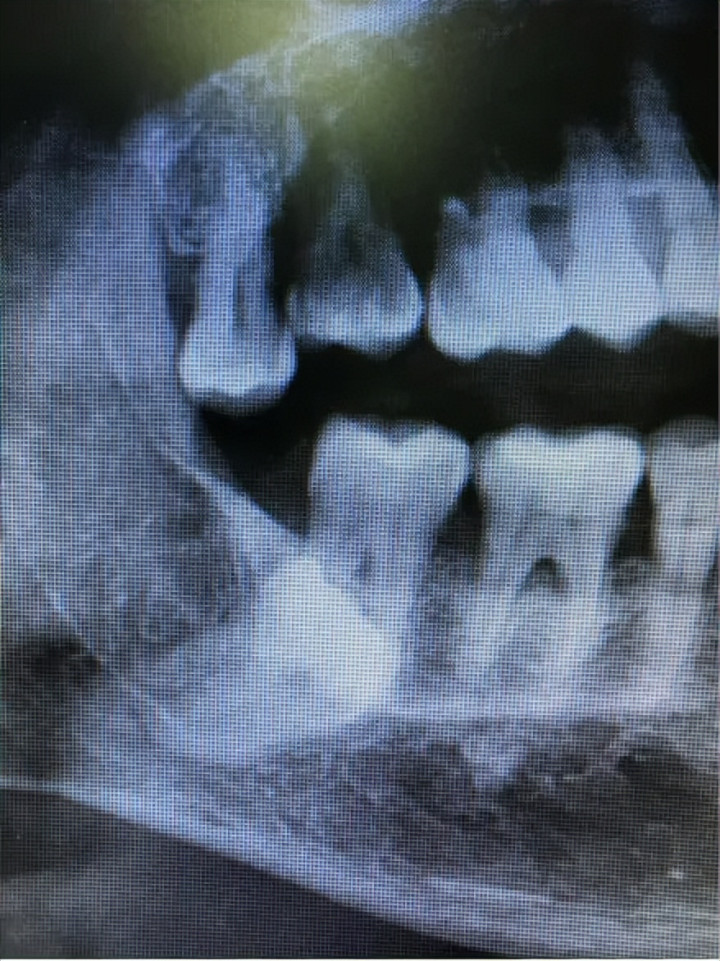

龋齿蛀得太深,细菌如故侵蚀到牙床,大致牙冠基本烂光,补牙、根管调理、牙套都无法支持。这种牙留着不仅没用,还可能成为“细菌窝”,激勉感染。

牙周病是牙齿的“隐形杀手”。当牙槽骨被炎症给与殆尽,牙齿松动得像风中的树叶,无法保留时。

智齿长歪、长不出来(阻生)、动不动就发炎肿痛,以至如故把邻牙顶坏、导致邻牙龋齿的,以至有引起囊肿、肿瘤风险。这种智齿留着是“定时炸弹”